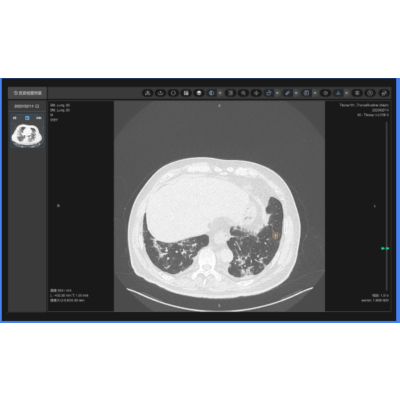

肺结节影像辅助分类诊断

精准识别、分割肺部各类结节灶,输出病灶定位、体积、倍增、密度、形态、征象等多元化参数,进行基于人工智能深度学习的病灶良恶性诊断,肺癌结节灶实现定性诊断。提供随诊复查功能系统,实现多次检查间病灶精准匹配,定量分析,帮助更方便地疾病监测、疗效评估。